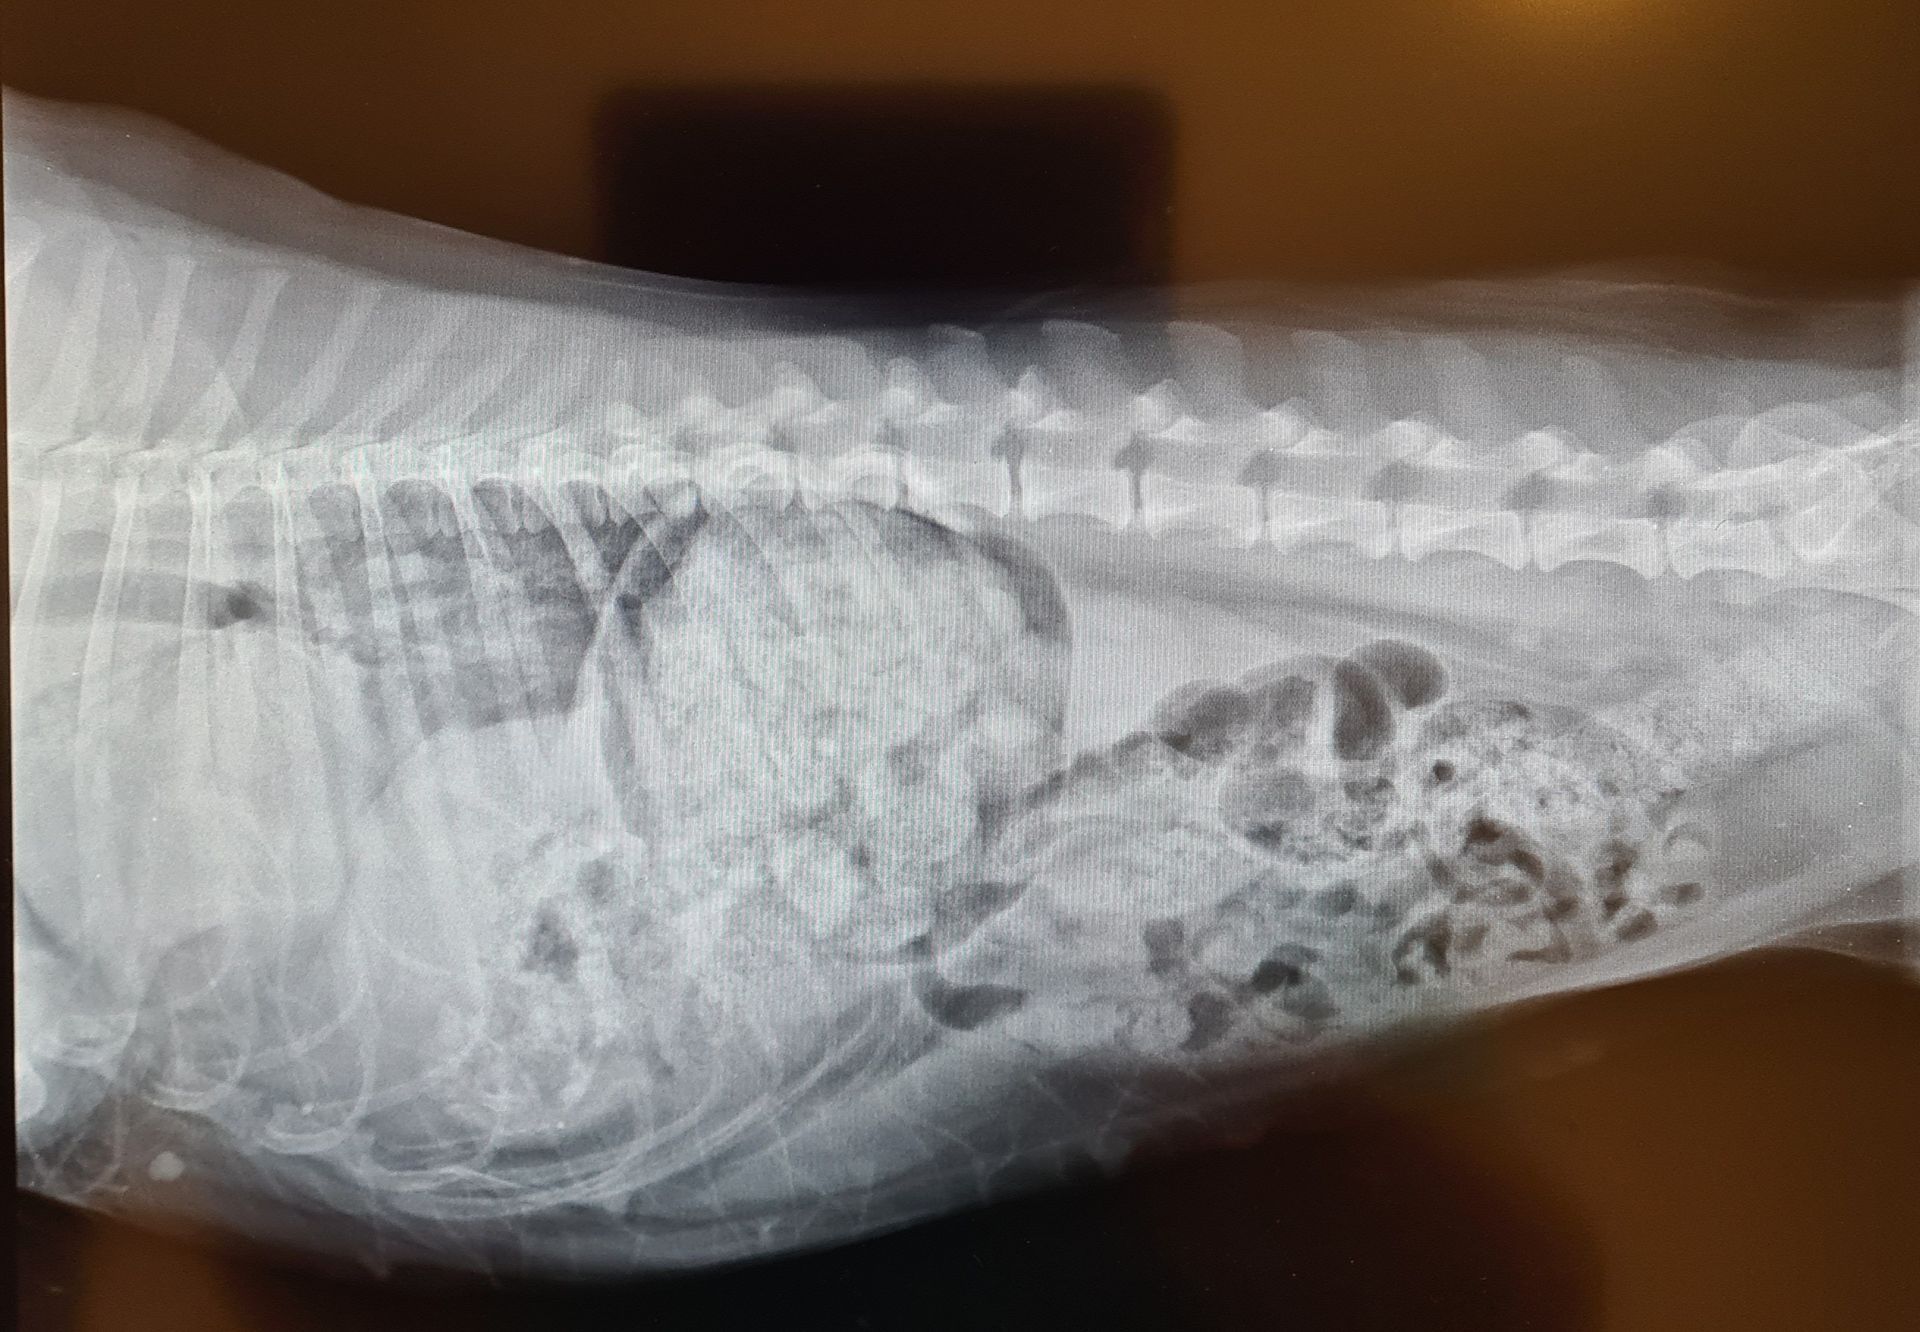

La radiologie

La clinique est équipée d'un générateur radio ainsi que d'un développement numérique. Ce type de développement est rapide, sans utilisation de produits chimiques et permet d'obtenir les images sur un écran d'ordinateur. La définition des radios est ainsi meilleure. Nous pouvons aussi facilement vous faire parvenir les radios de votre animal ou les transférer à un confrère le cas échéant par mail.

- Radios classiques

- Radios avec produit de contraste